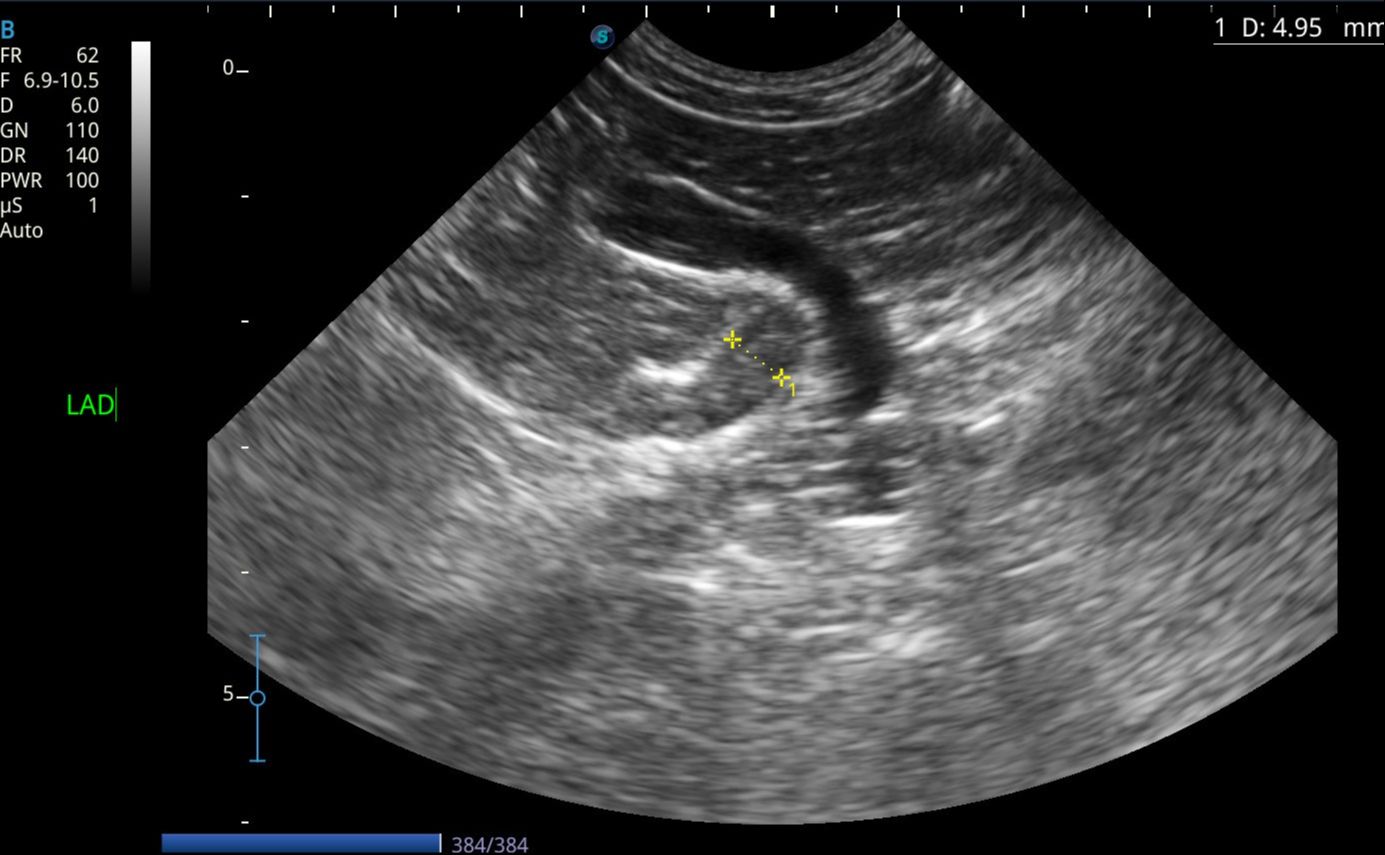

Images from the X5V